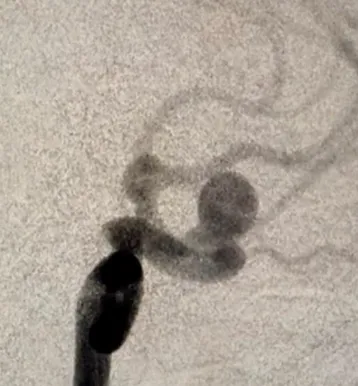

Aneurysms of cerebral arteries are vascular pathologies in which the wall of an artery bulges. According to the shape of the protrusion, saccular and spindle-shaped (fusiform) aneurysms are distinguished. The cause of aneurysms is not known for sure. Among the etiological factors can be congenital predisposition (defects of the muscle layer of the wall of cerebral vessels); atherosclerotic (combined with congenital defects of the wall of cerebral vessels); embolic, infectious, traumatic factors.

Brain MRI, cerebral angiography, CT angiography.

If uncomplicated aneurysms are detected, planned neurosurgical intervention is carried out using the methods of aneurysm clipping or balloon angioplasty (endovascular closure of the protrusion of the vessel wall).